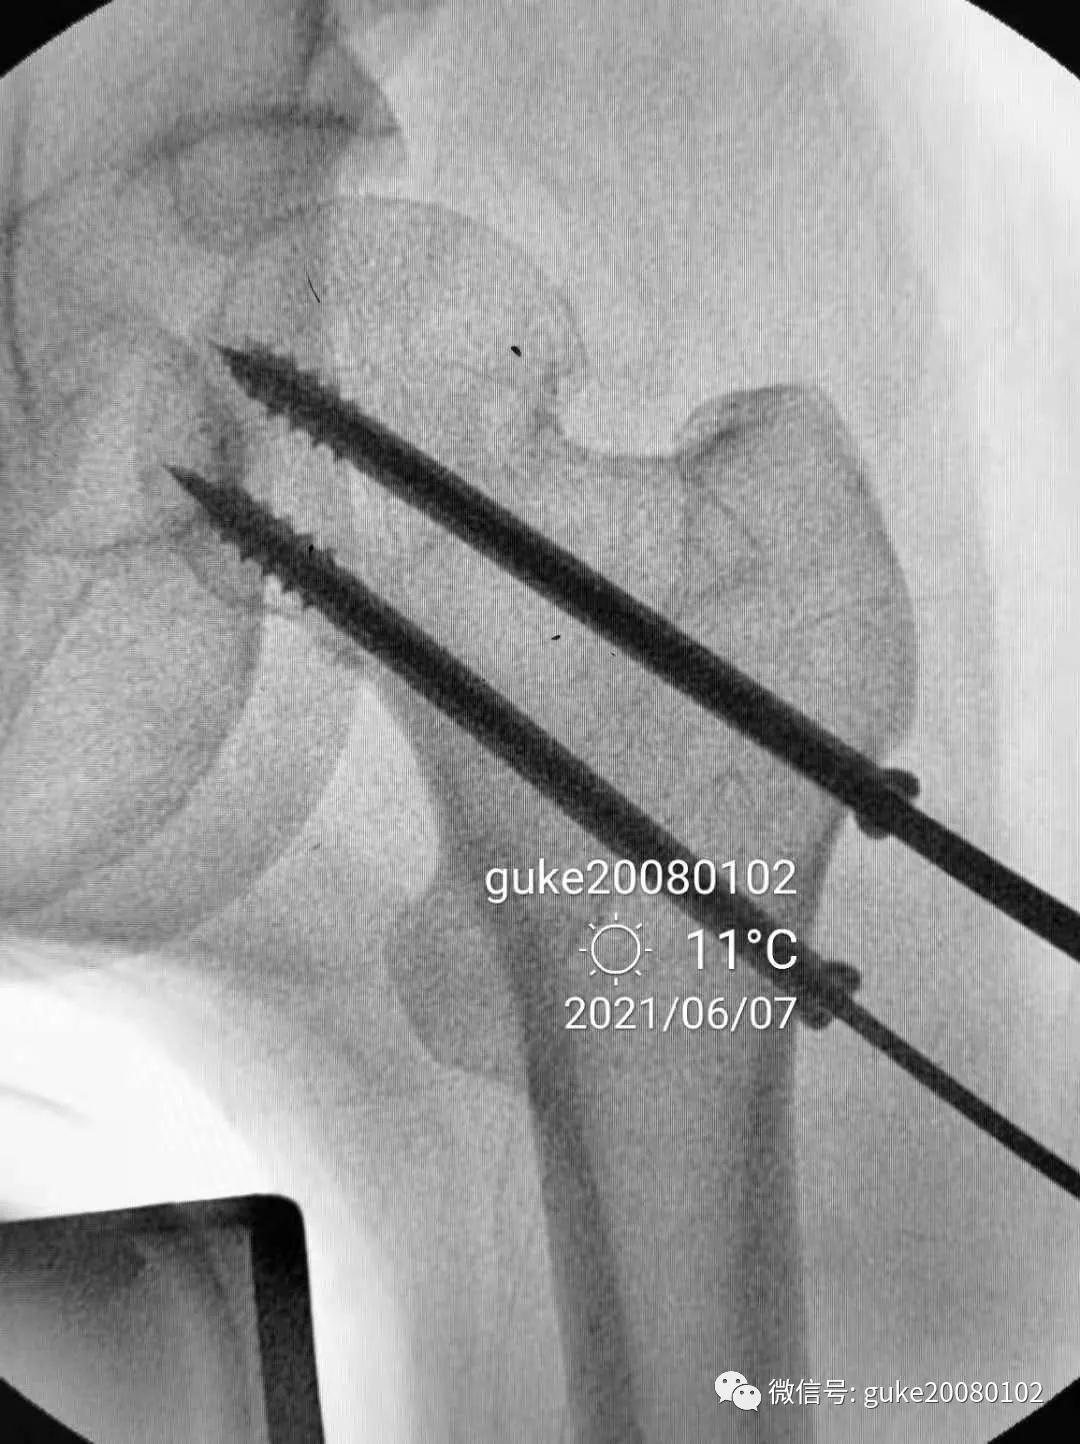

1、植入的第一枚克氏针,前倾和颈干角均满意。将其作为标志针。

2、植入第二枚导针,调整前倾和颈干角。

3、数次调整三枚导针到最合适的位置。